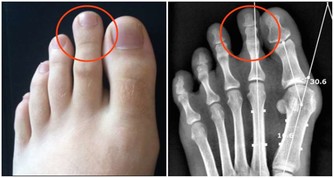

愛喝啤酒如果已經患了腎臟方面的疾病,又經常大量喝啤酒,

會使尿酸沉積導致腎小管阻塞,造成腎臟衰竭。